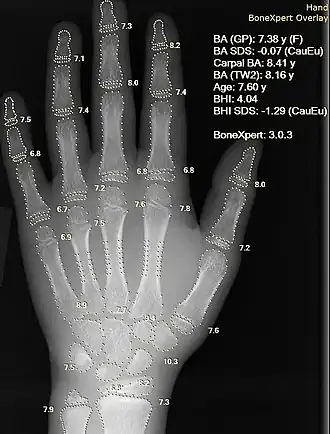

L'informatique médicale est l'application des techniques issues de l'informatique au domaine médical. L'informatique médicale est une science à part entière ; aux confluents des sciences de l'information et de la médecine, c'est aussi l'une des technologies nécessaire au développement de l'E-médecine. Elle permet d'affiner et d'accélérer ou automatiser certains moyens d'investigation médicale et de diagnostic. Elle apporte de nouveaux mécanismes et moyens d'interprétation et de raisonnement médical, d'abstraction et d'élaboration des connaissances, de mémorisation et d'apprentissage ; parfois en s'appuyant sur des démarches Open Source[1], notamment dans le domaine de la « recherche en santé Informatique translationnelle »[2].